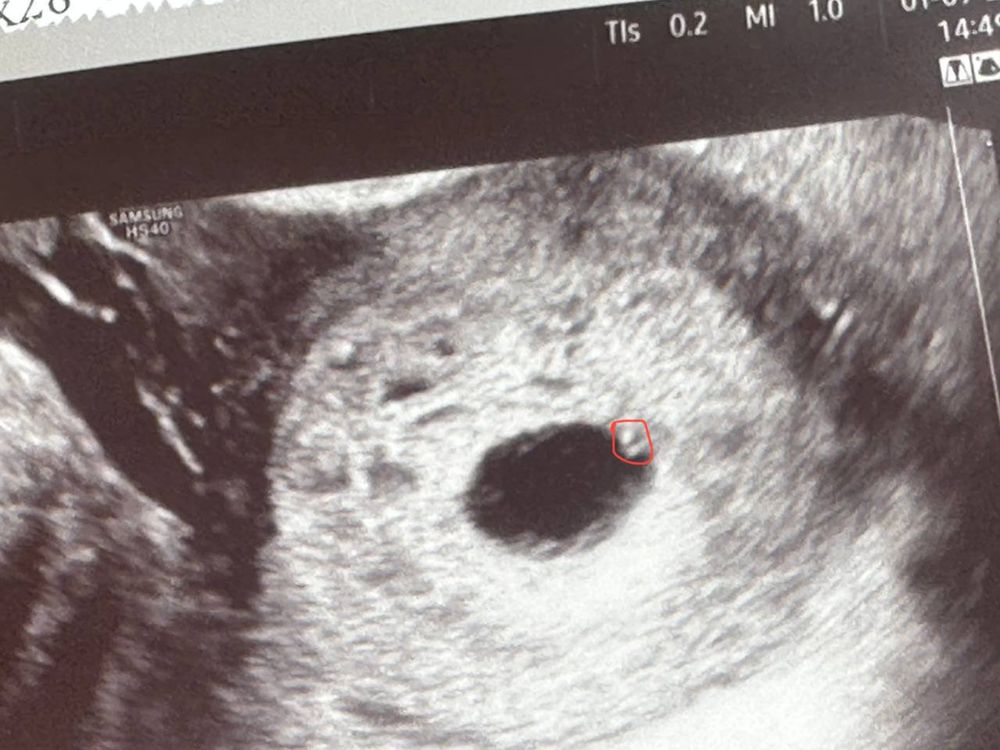

4. По узи от 17.08 - плодный мешок 5.6 мм

25.08 -плодный мешок 10.5 мм + хорион кольцевидный + желточный мешок 3 мм

01.09 - плодный мешок 12.8 мм + желточный мешок 2 мм

За неделю пя почти не выросло. Да и с таким хгч пора быть эмбриону и сб.. Как правило ждут эмбрион до размера 25 мм у пя. Но здесь скорее замершая.

У вас срок уже большой,вы писали хгч 11.08 -4,3 акушерских это 17 дпо получается,хгч соответствует данному дпо и 1 сентября у вас уже 38 дпо,а это 7+3 акушерских, эмбрион ещё неделю назад должен был быть,а у вас и пя плохо растет и до 25 мм оно просто не дорастет,в вашем случае это анэмбриония, крайний срок для эмбриона 35 дпо и 7 акушерских и на этом сроке он уже не меньше 7 мм с сб